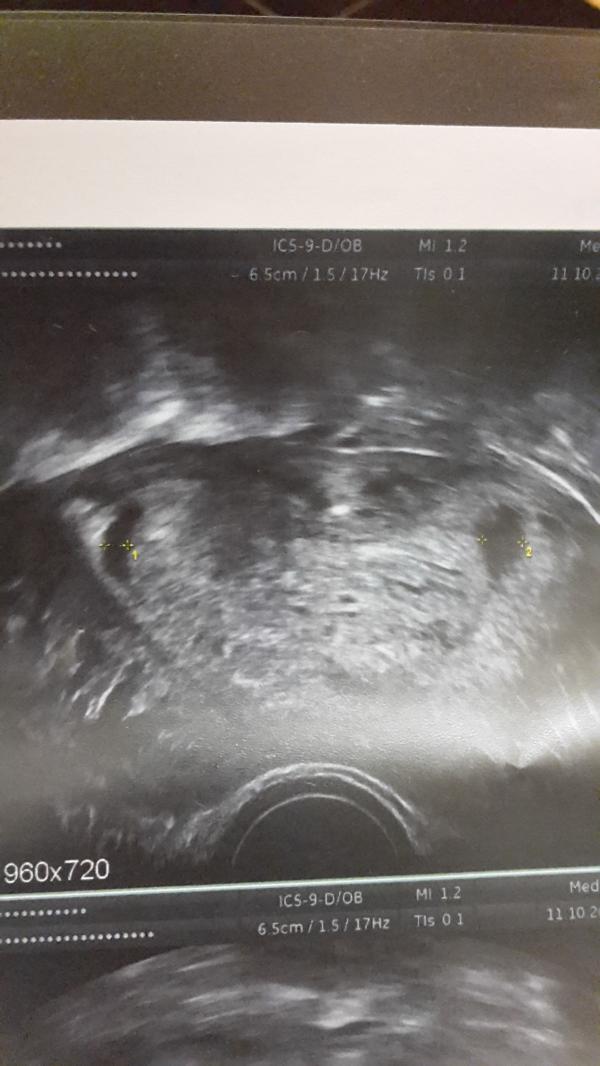

Девчонки, может кто сталкивался с гематомами в области трубных углов матки при беременности? ( это из матки в трубы переход )

@oh.my.momlife, вот и у меня такая как у вас

@mari-l у меня была гематома, но ретрохориальная. А это что -то другое. С чем врачи связывают это?